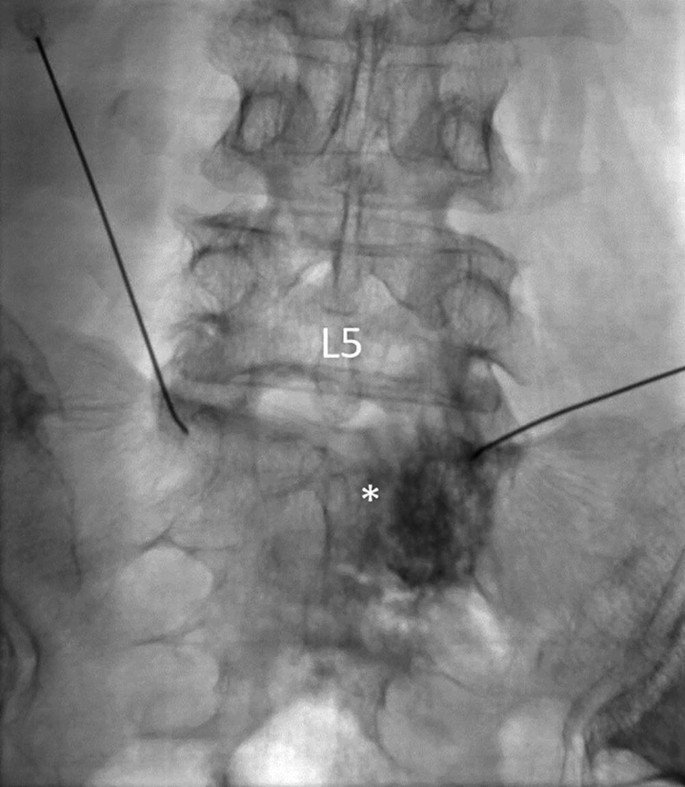

Superior Hypogastric Plexus and Ganglion Impar Block ...

Cureus | Efficacy of Pudendal Nerve Blocks and Ultrasound ...